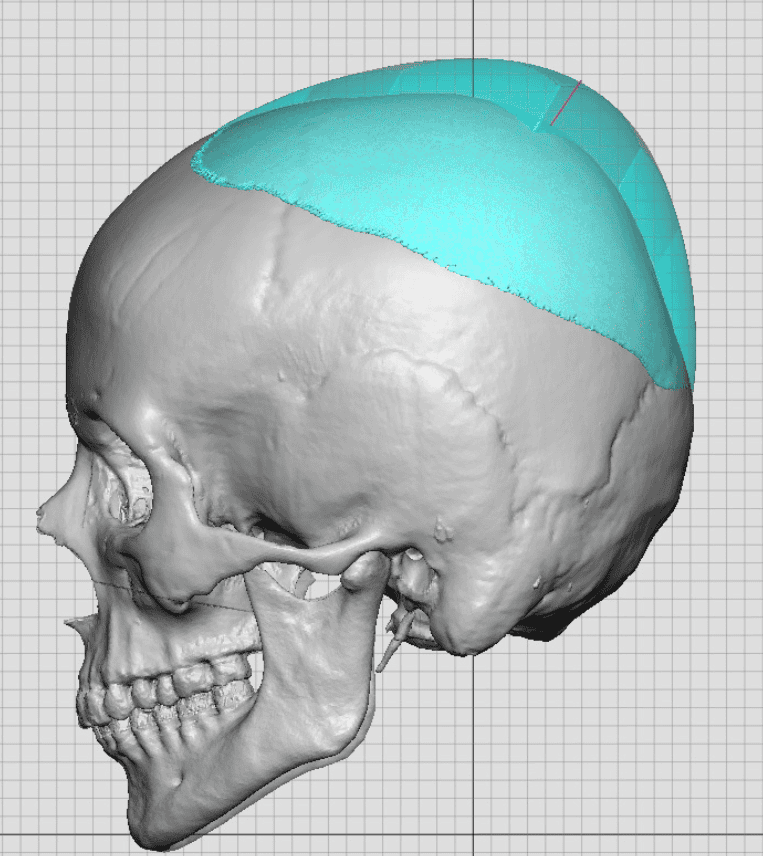

Severe narrowing skull deformity from prior sagittal craniosynostosis repair as an adult.

Complete replacement of entire skull by a custom implant with temporal fat injections.

Severe narrowing skull deformity from prior sagittal craniosynostosis repair as an adult.

Complete replacement of entire skull by a custom implant with temporal fat injections.